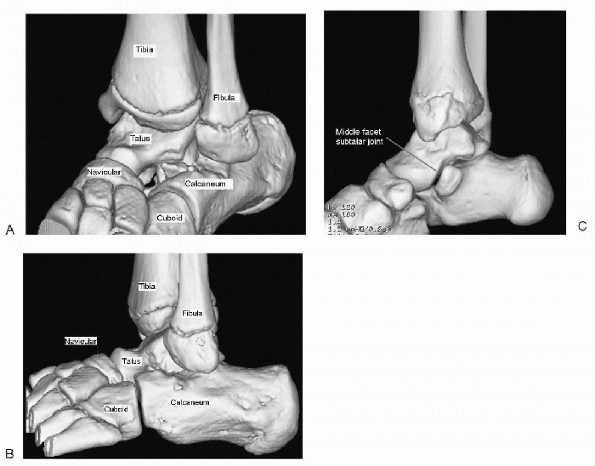

of the hindfoot is complicated. The two bones below the ankle joint lie

on top of each other—the talus above and the calcaneus below. They meet

at the subtalar joint, which has three facets—posterior, middle, and

anterior. Distal to this are two bones that lie side by side: the

navicular on the medial side and the cuboid on the lateral side. The

anterior calcaneus articulates with the cuboid, and the anterior talus

articulates with the navicular.

![]() |

Figure 4.4-1

Normal osseous anatomy of the hindfoot taken from a threedimensional computed tomography reconstruction as seen from the dorsolateral side of the left foot (A), the lateral side of the left foot (B), and the medial side of the right foot (C). |

and calcaneus (i.e., bridging the middle facet) and between the

calcaneus and the navicular (which do not normally form an